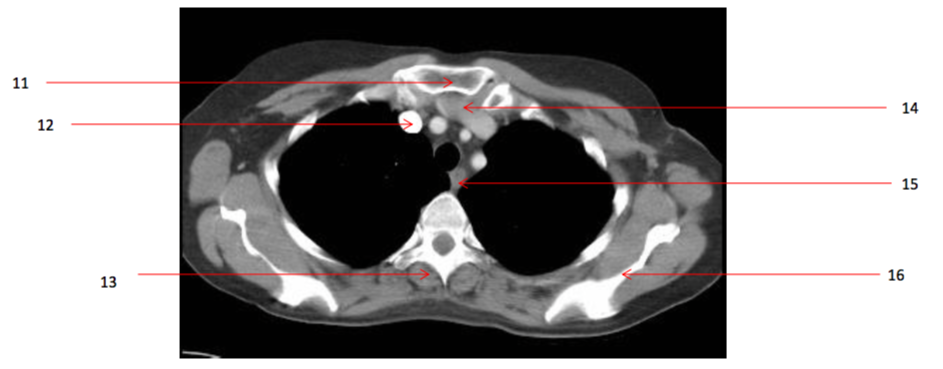

Number 14?

Lt brachiocephalic vein

Number 11?

Sternum (manubrium)

Number 12?

Rt brachiocephalic vein

Number 13?

Rt erectae spinae muscle

Number 16?

Lt scapula